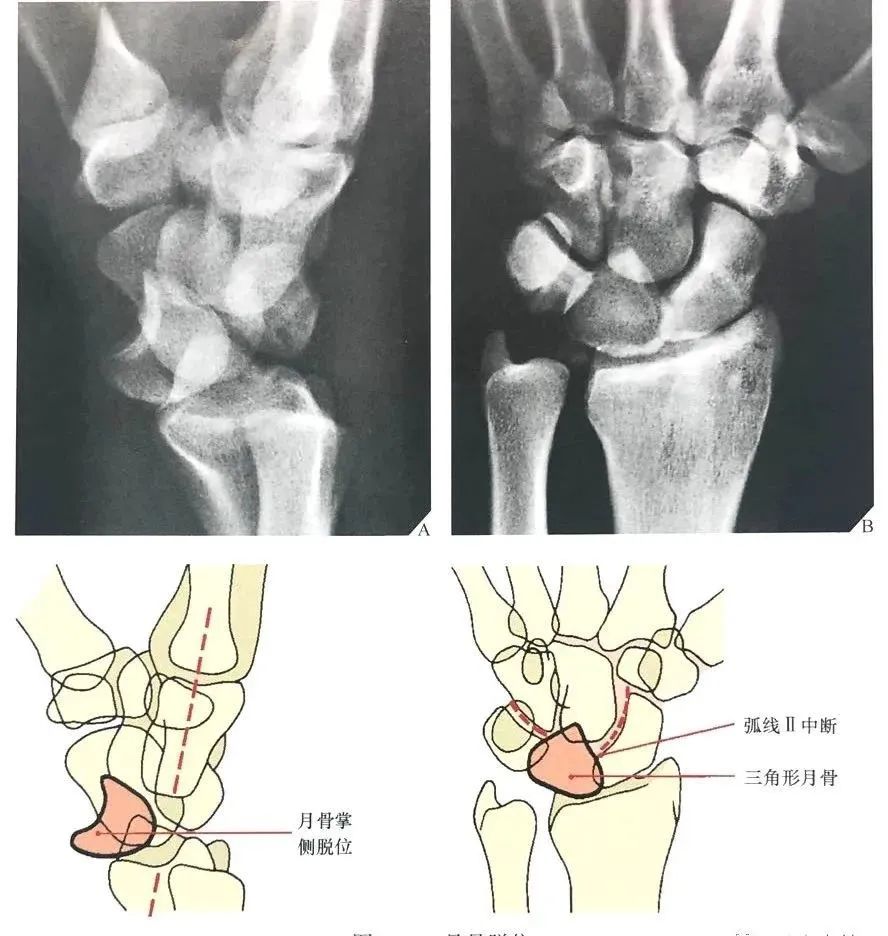

图21 左:月骨脱位;右:月骨周围脱位

月骨和月骨周围脱位:腕关节中立位置的背掌位和侧位X线片足以诊断月骨和月骨周围脱位。侧位像可以清晰显示在桡骨远端上方的月骨、头状骨和第三掌骨长轴呈直线状排列,这条线任何一点的中断都能确定半脱位或脱位的诊断。

当头状骨保持在直线上,一旦月骨成角度离开桡骨远端表面,月骨脱位即可被识别(图22A)。

同样的,在背掌位投照时,由舟骨远端凹面、月骨、三角骨所构成的弧线 II 的中断和相伴随的月骨三角形外观也可以诊断月骨脱位(图22B), 月骨脱位也能有效地从CT上显示,尤其是3D CT的重建图像(图23)。

图22 月骨脱位。(A)在腕关节侧位像上,月骨脱位时脱离由第三掌骨、头状骨和桡骨远端的长轴排列,月骨向掌侧旋转和移位。(B)背掌位投照显示弧线 II 在月骨位置中断。注意月骨的三角形外观及月骨脱位的征象。